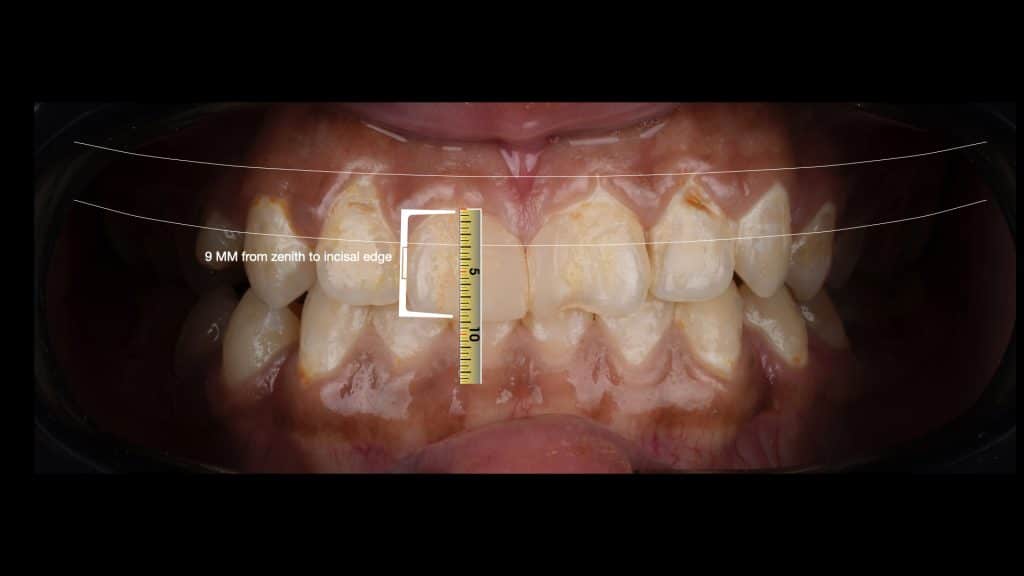

we measure the length of the right central to calibrate the ruler in Keynote

we will need 2.5mm to be removed from the gum starting from the incisor and keep on to other teeth

we have to make bone sounding (measure the distance from the free gingival margin to the bone level) to see how much we can remove

everything look perfect, we need to remove 2.5mm from the gum and we had 5 mm to the bone crest, so we can remove 2.5mm and then new gingival margin will be 2.5mm to the bone crest and that's not a problem since she had medium thick biotype.

no need for bone removal